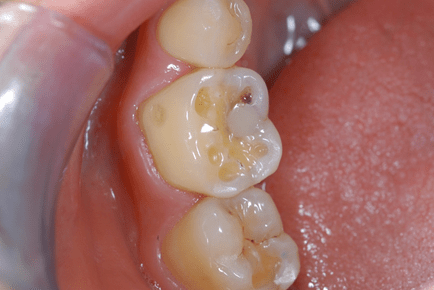

Every time you eat, your teeth are exposed to acids and bacteria. Sugary and starchy foods feed harmful bacteria in the mouth, leading to plaque formation.

Over time, poor diet and dental health habits can cause:

- Tooth decay

- Gum disease

- Enamel erosion

Sugar feeds bacteria that produce acid, leading to cavities.

- Frequent cavities

- Tooth sensitivity